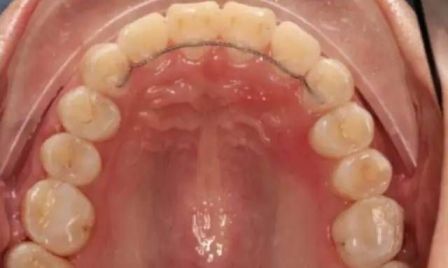

舌侧固定保持器

正畸是个慢慢施力,让牙齿缓慢移动的过程。对于青少年来说,整个正畸带牙套的过程大概持续1年多,而对于成年人来说,可能会持续两年甚至更久。但是,取下牙套,并不是万事大吉了。因为牙齿已经在原来位置待了几十年的时间,仅仅通过两年的力量,虽然它到达了新的位置,但是它还是有回复原位的趋势。因此摘下牙套后,必须佩带保持器。

佩带保持器的前半年,一般是要整天佩带,之后可能变为仅需要晚上佩带。而且现在有一种装在舌侧的保持器,细细一根,可以一直固定,不用摘掉,对美观和各种口腔活动也没有明显影响。所以建议大家一定要按医生要求,坚持佩带保持器。